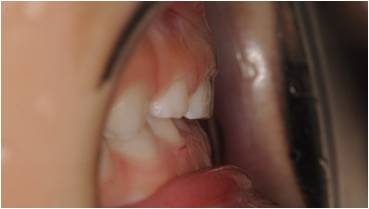

治療後

受け口の小児矯正治療(7歳の女子)の治療前後の写真です。矯正治療によって下顎前突(受け口)と上顎の狭さが改善され、正しい咬合に導かれています。